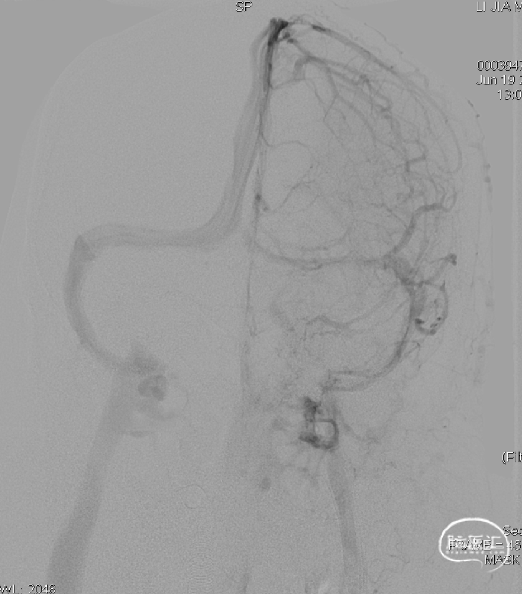

左侧咽升供血的HCDAVF,逆流至海绵窦,经眼上静脉-面静脉引流。

Echelon微导管超选面静脉,后通过眼上静脉超选至海绵窦,进一步超选至瘘口,微导管造影确认在位。

三枚弹簧圈对瘘口进行填塞,后通过Echelon微导管进行缓慢注胶,中途反复确认注胶形态。